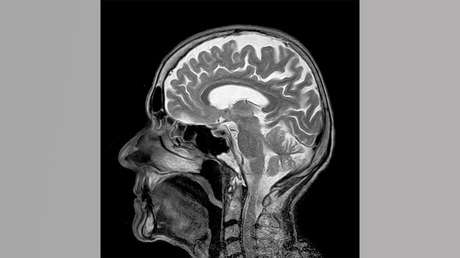

De acuerdo con la cadena, el fármaco experimental llamado BAN2401 parece haber eliminado el amiloide, una proteína que es el sello distintivo de la enfermedad de Alzheimer. Todos los ensayos anteriores que atacan el amiloide, incluso algunos que cuestan cientos de millones de dólares, han fallado en los pacientes. El nuevo estudio sugiere ese fracaso se debe a que fue administrado tarde y en cantidades insuficientes.

Según los representantes de la compañía estadounidense Biogen, que está desarrollando el fármaco junto con la empresa japonesa Essai, dieciocho meses después de haber empezado a tomar el fármaco los pacientes que recibieron la dosis más alta experimentaron una caída dramática del amiloide en sus cerebros y dieron señales de que la progresión de la enfermedad se había ralentizado.

Aunque los fármacos antiamiloides se consideran aún los más prometedores para tratar formas tempranas de la enfermedad de Alzheimer, los investigadores también están desarrollando medicamentos candidatos que actúan sobre otros aspectos de la enfermedad. Así, una tomografía por emisión de positrones, o PET experimental, puede visualizar la acumulación de otra proteína característica del alzhéimer, llamada tau.